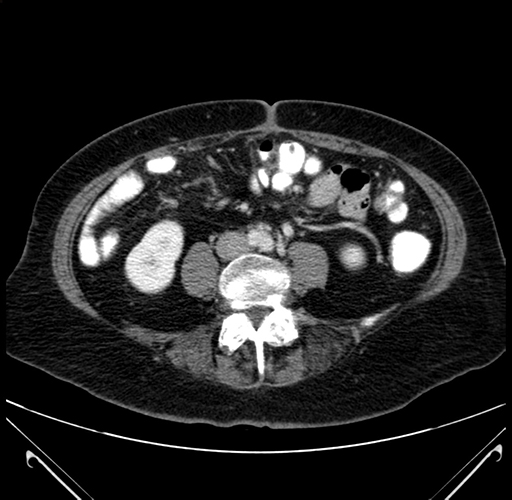

Pre-Chemo: Axial Venous